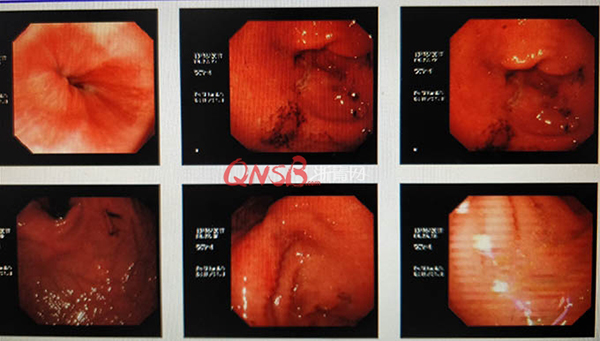

接診醫(yī)生在詳細詢問了病史后,懷疑小周的腹痛可能不僅是急性胃炎那么簡單,建議他做個胃鏡檢查。檢查結果出來后,小周大吃一驚,本以為自己的胃很健康,卻不想胃粘膜廣泛充血糜爛,長了兩個巨大的潰瘍(直徑大于2厘米),還有出血和咖啡色血痂。

檢查結果出來后,小周大吃一驚,本以為自己的胃很健康,卻不想胃粘膜廣泛充血糜爛,長了兩個巨大的潰瘍(直徑大于2厘米),還有出血和咖啡色血痂。